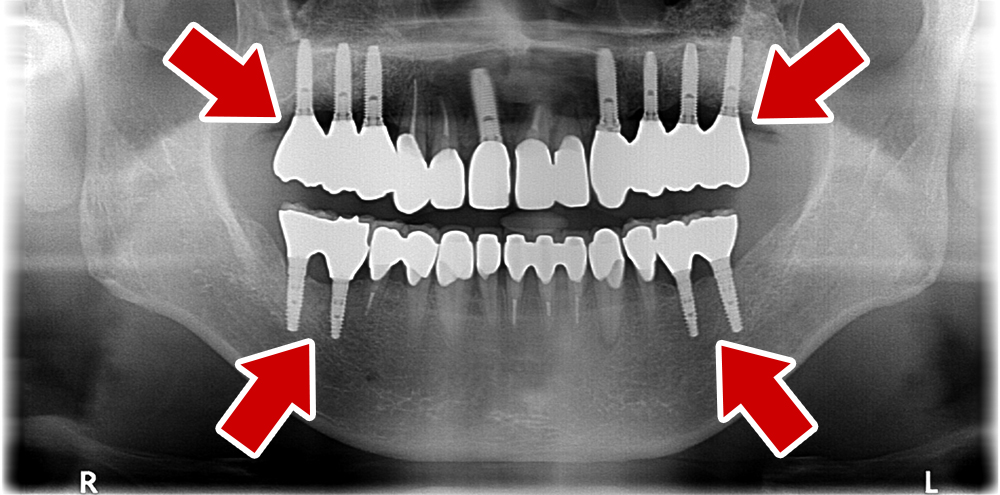

55歳 男性

- 主訴

- 前歯でしか咬めなく、食事を採るのに非常に困難で辛い

- 処置内容

- 上顎6本、下顎3本

- 治療費用

- 上顎:約230万(税込)下顎:約120万(税込)

- 治療期間

- 上顎:1年(仮歯まで8か月)下顎:8か月(仮歯まで5か月)

- リスク

- 上部構造物、仮歯の破折、術後の腫れ(3日)、人工歯根脱落リスクがあります